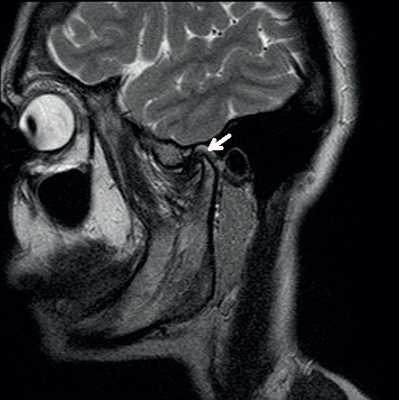

«Застрявший» диск.

«Застрявший» диск. PD sag изображения с открытым (А) и закрытым (Б) ртом - задний край диска (стрелка) остается в нижнечелюстной ямке височной кости. По этой причине открывание рта сильно ограничено. Вероятная причина - образование спаек.